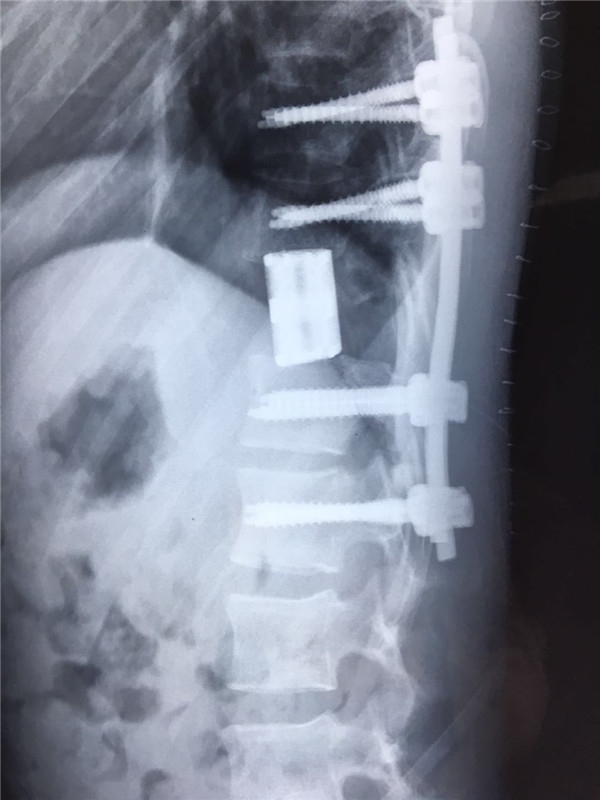

术后 侧位